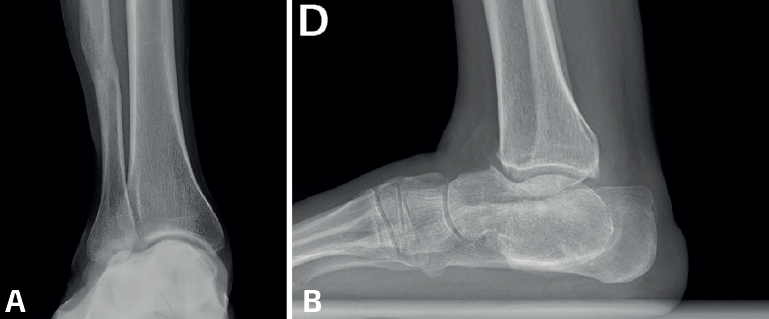

La mayoría de las coaliciones atípicas se diagnostican como hallazgos casuales al solicitar radiografías simples en pacientes con dolores en los pies, generalmente con deformidad en plano valgo. Las proyecciones convencionales –dorsoplantar y lateral– de ambos pies en carga suelen poner ya de manifiesto coaliciones atípicas como las talonaviculares y las calcaneocuboideas. Las proyecciones oblicuas son importantes porque suelen mostrar algunas coaliciones como las naviculocuboideas, las cuneometatarsianas y las coaliciones tarsales masivas. Las radiografías de ambos tobillos en carga suelen mostrar la consecuencia de algunas coaliciones tarsales masivas en forma de tobillo en cúpula (ball-and-socket)(13). Se han descrito varios signos radiológicos asociados a las coaliciones atípicas, como el “signo de la seta” en las talonaviculares, aunque algunas coaliciones atípicas presenten signos ya conocidos en las típicas, como el talar beak en las calcaneocuboideas o el del “oso hormiguero” en las naviculocuboideas(14)(Figura 1).